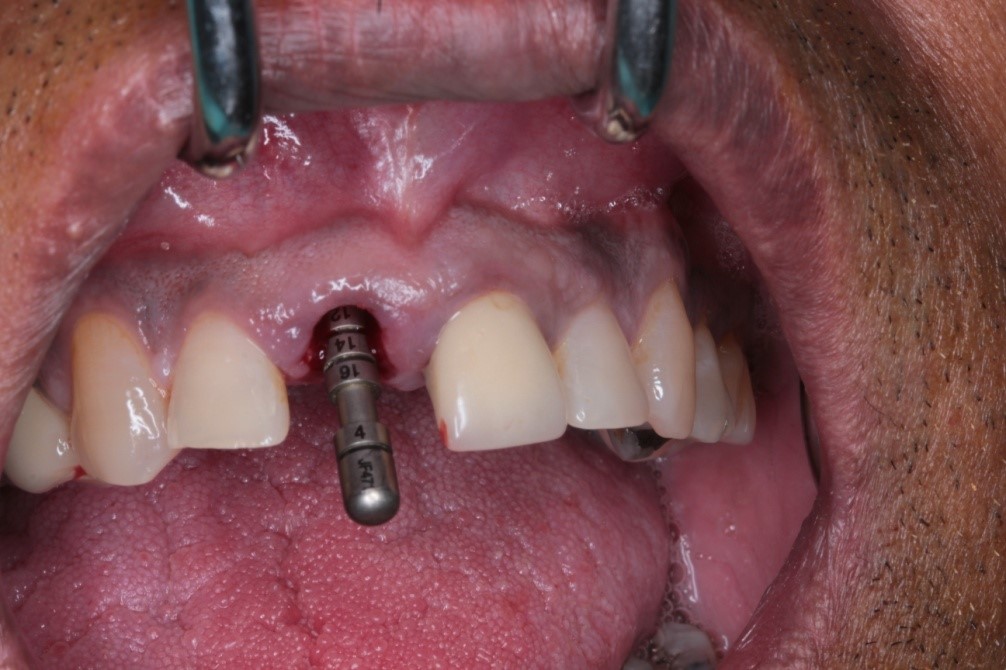

Once Dr Bagasi drilled the correct sized hole in the jaw, a tool was used to measure the exact depth of the hole. This is important, as the hole needs to be the correct depth in the jaw for the bone to attach onto the implant.

Once the implant had been fitted and Dr Bagasi was happy with the placement in the jaw, a healing cap was attached on to the end of the implant. This is done to assure that the soft tissue does not heal over the implant itself when we come to attaching the crown.